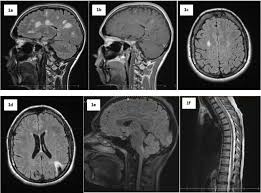

Multiple sclerosis (ms) is a chronic inflammatory, demyelinating, and neurodegenerative disorder of the central nervous system (cns) that affects the white and grey matter of the brain, spinal cord, and.

Multiple sclerosis (abbreviated ms, known as disseminated sclerosis or encephalomyelitis disseminata) is an inflammatory disease in which the fatty myelin sheaths around the axons of the. Multiple sclerosis (ms) is a chronic autoimmune debilitating disease in which nerve damage (demyelination of neurons) in the brain and spinal cord disrupts their communication with the body. Multiple sclerosis information including symptoms, diagnosis, treatment, causes, videos, forums, and local community support. Find answers to health issues you can trust from healthgrades.com. Ms causes gradual destruction of myelin (demyelination) and breakdown of neuronal axons throughout the brain and spinal cord.

Ms causes gradual destruction of myelin (demyelination) and breakdown of neuronal axons throughout the brain and spinal cord. Find answers to health issues you can trust from healthgrades.com. Multiple sclerosis (ms) symptoms, causes, treatment, life expectancy. Multiple sclerosis (ms) is a chronic inflammatory disease in which the myelin sheath on the nerve endings gets inflamed and damaged. Read current research articles and learn about multiple sclerosis diagnosis, symptoms as well as the latest ms treatment options. In ms , the immune system attacks the protective sheath (myelin) that covers nerve fibers. Multiple sclerosis (ms) is an autoimmune disease in which the body's immune system attacks its multiple sclerosis is estimated to affect 2.8 million people worldwide. Multiple sclerosis (ms) is thought to be an autoimmune disease;